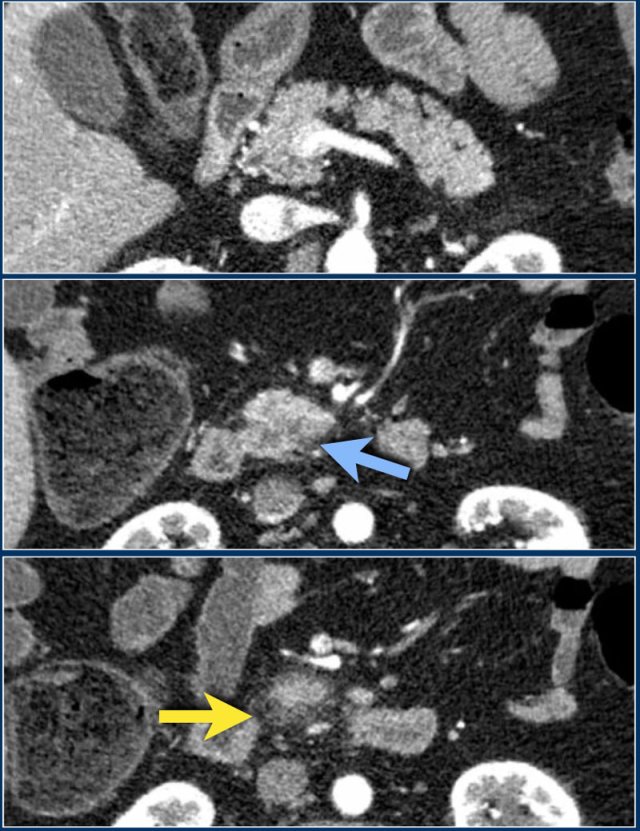

These images are of a patient who presented with acute severe epigastric pain very suggestive of acute pancreatitis.

However the amylase level was within normal levels.

A CECT was performed.

The findings are:

- Most of the pancreas is normal.

- Some edema of the uncinate process of the pancreatic head (blue arrow).

- Edema in the peripancreatic fat (yellow arrow), consistent with interstitial pancreatitis.

There were no complications and the diagnosis of mild pancreatitis was made.